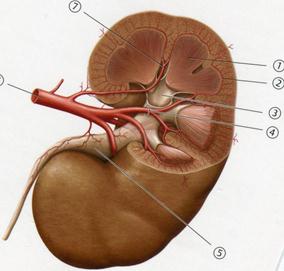

С. Жоғарғы қуыс

В. Денесі